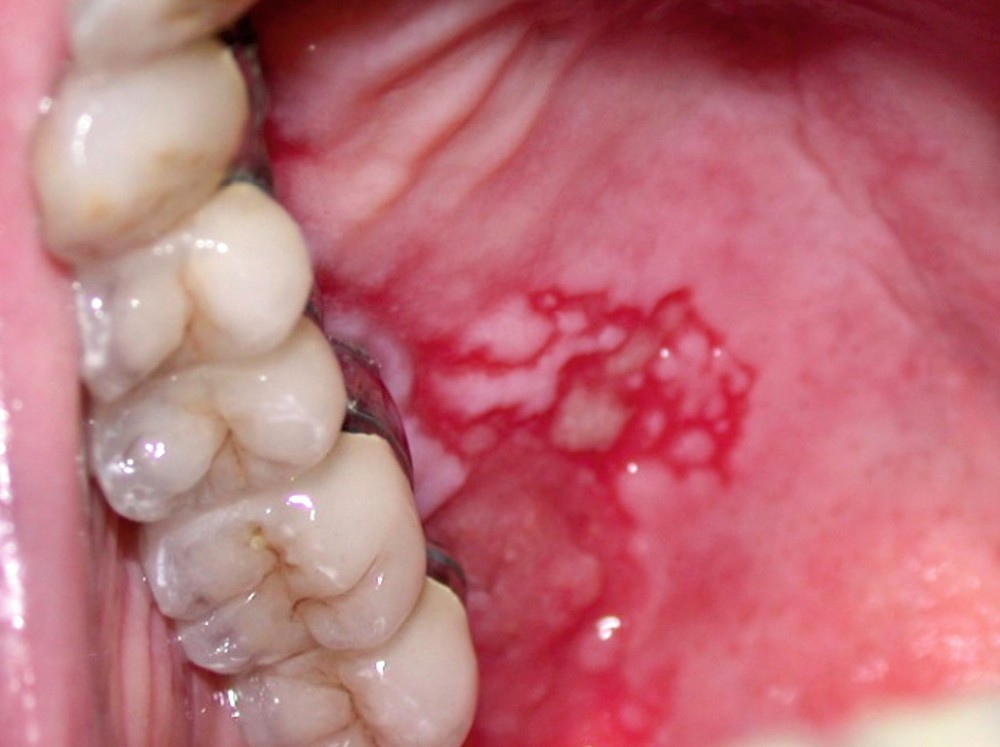

Érythroplasie associée à un lichen oral : elle se caractérise par des lésions kératinisées plus ou moins réticulées ou sous forme de plages et plaques associées à une macule, plage, plaque érythémateuse bien limitée (fig. 3).